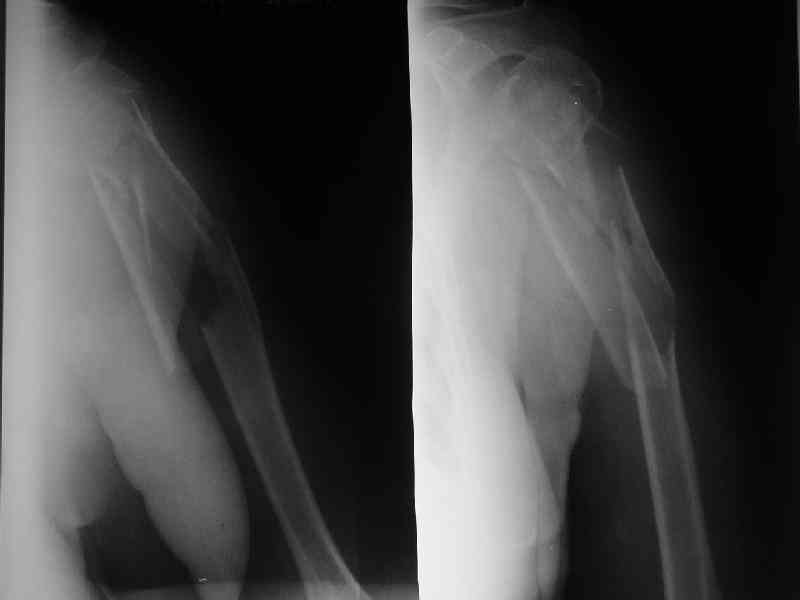

Здесь нет необходимости в серкляже. Вмешиваться на промежуточных отломках приходится, если есть угроза перфорации кожи, или промежуточный отломок попал в фасцию, как пуговица в петлю. В приложении сегментарный оскольчатый перелом плеча в проксимальном отделе, фиксированный больщеберцовым стержнем. Как видите, обошлось без серкляжа. Функция полная.

Пример отличный.

Вот что значит лечить перелом, а не рентгенограмму!

Александр, великолепные снимки! Вопрос - что за гвоздь?

Это укороченный большеберцовый стержень, которые делает предприятие "ЦИТО".

на синтезовский UTN похож))

Скажите пожалуйста, Александр Николаевич, почему Вы использовали большеберцовый гвоздь?

Доступные на тот момент гвозди для плеча имели худшие возможности фиксации в коротком проксимальном отломке.

Уважаемый Александр Николаевич! На продемонстрированных вами рентгенограммах имеется достаточно большое на мой взгляд смещение отломков после фиксации блокируемым гвоздем. На счет полной функции все понятно, а нет ли каких либо сосудистых расстройств конечности? Имею ввиду венозную недостаточность или лимфостаз.